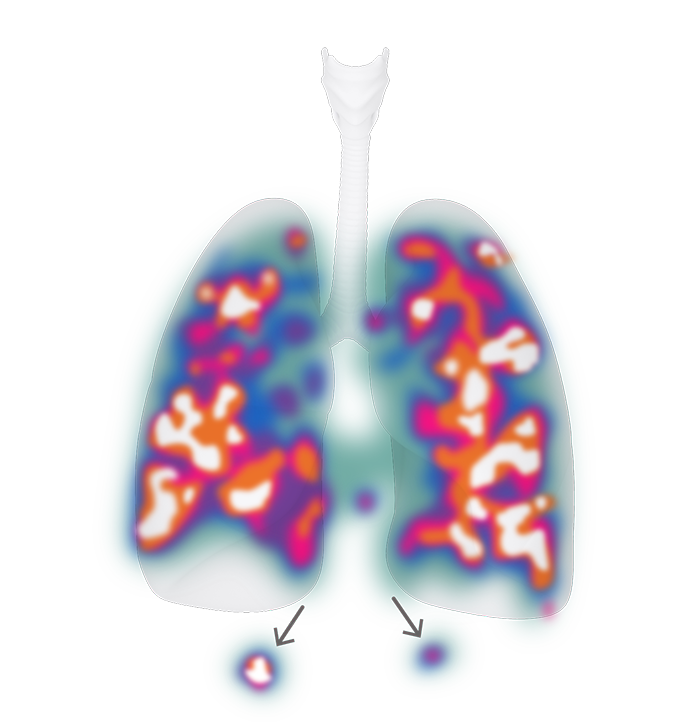

在健康受试者中,高流量雾化期间使用 Aerogen 给药的肺内沉降率 (3.6%) 比使用射流雾化器 (1.0%) 多 4 倍;P<0.05。†9

健康受试者在高流量氧疗期间通过 Aerogen 给药后,对放射性标记气雾剂沉降物进行 SPECT-CT 分析的代表图像.9

在健康受试者中,使用管路内 Aerogen 雾化器与使用射流雾化器的肺内沉降率之对比9